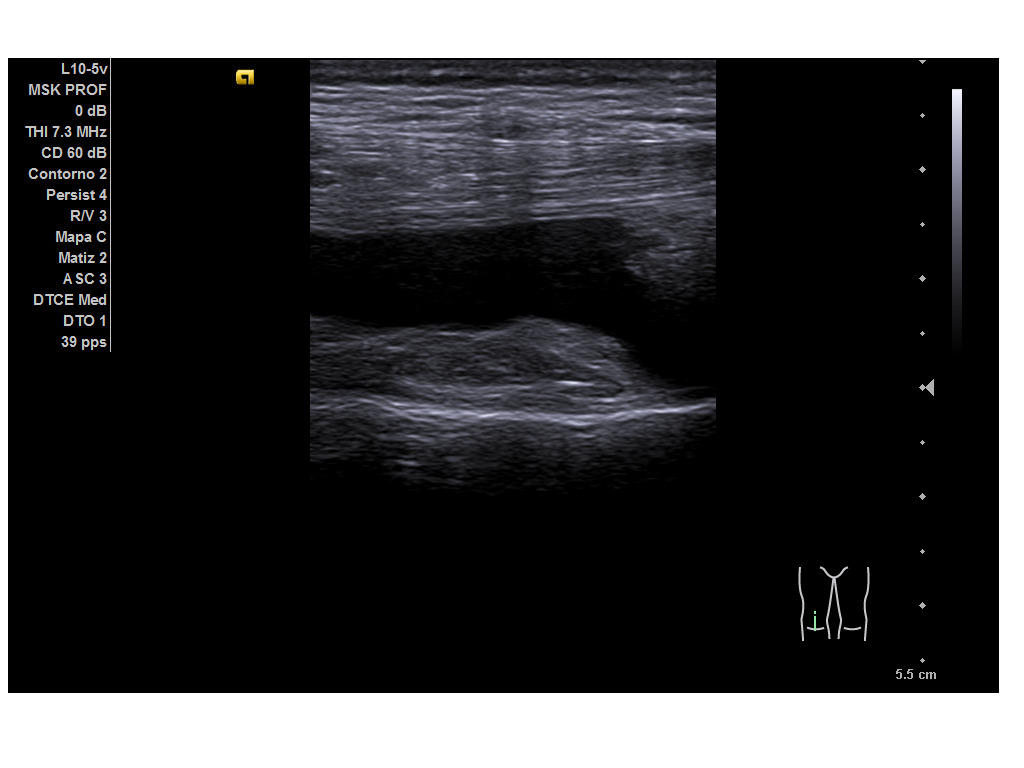

Durante la ecografía se observa una imagen anecoica suprarrotuliana, bajo el tendón del cuádriceps, compatible con una bursitis suprarrotuliana a nivel de la porción medial del cóndilo femoral medial de la rodilla derecha tanto en cortes transversales como longitudinales. Resto de las imágenes obtenidas se encontraban dentro de la normalidad.